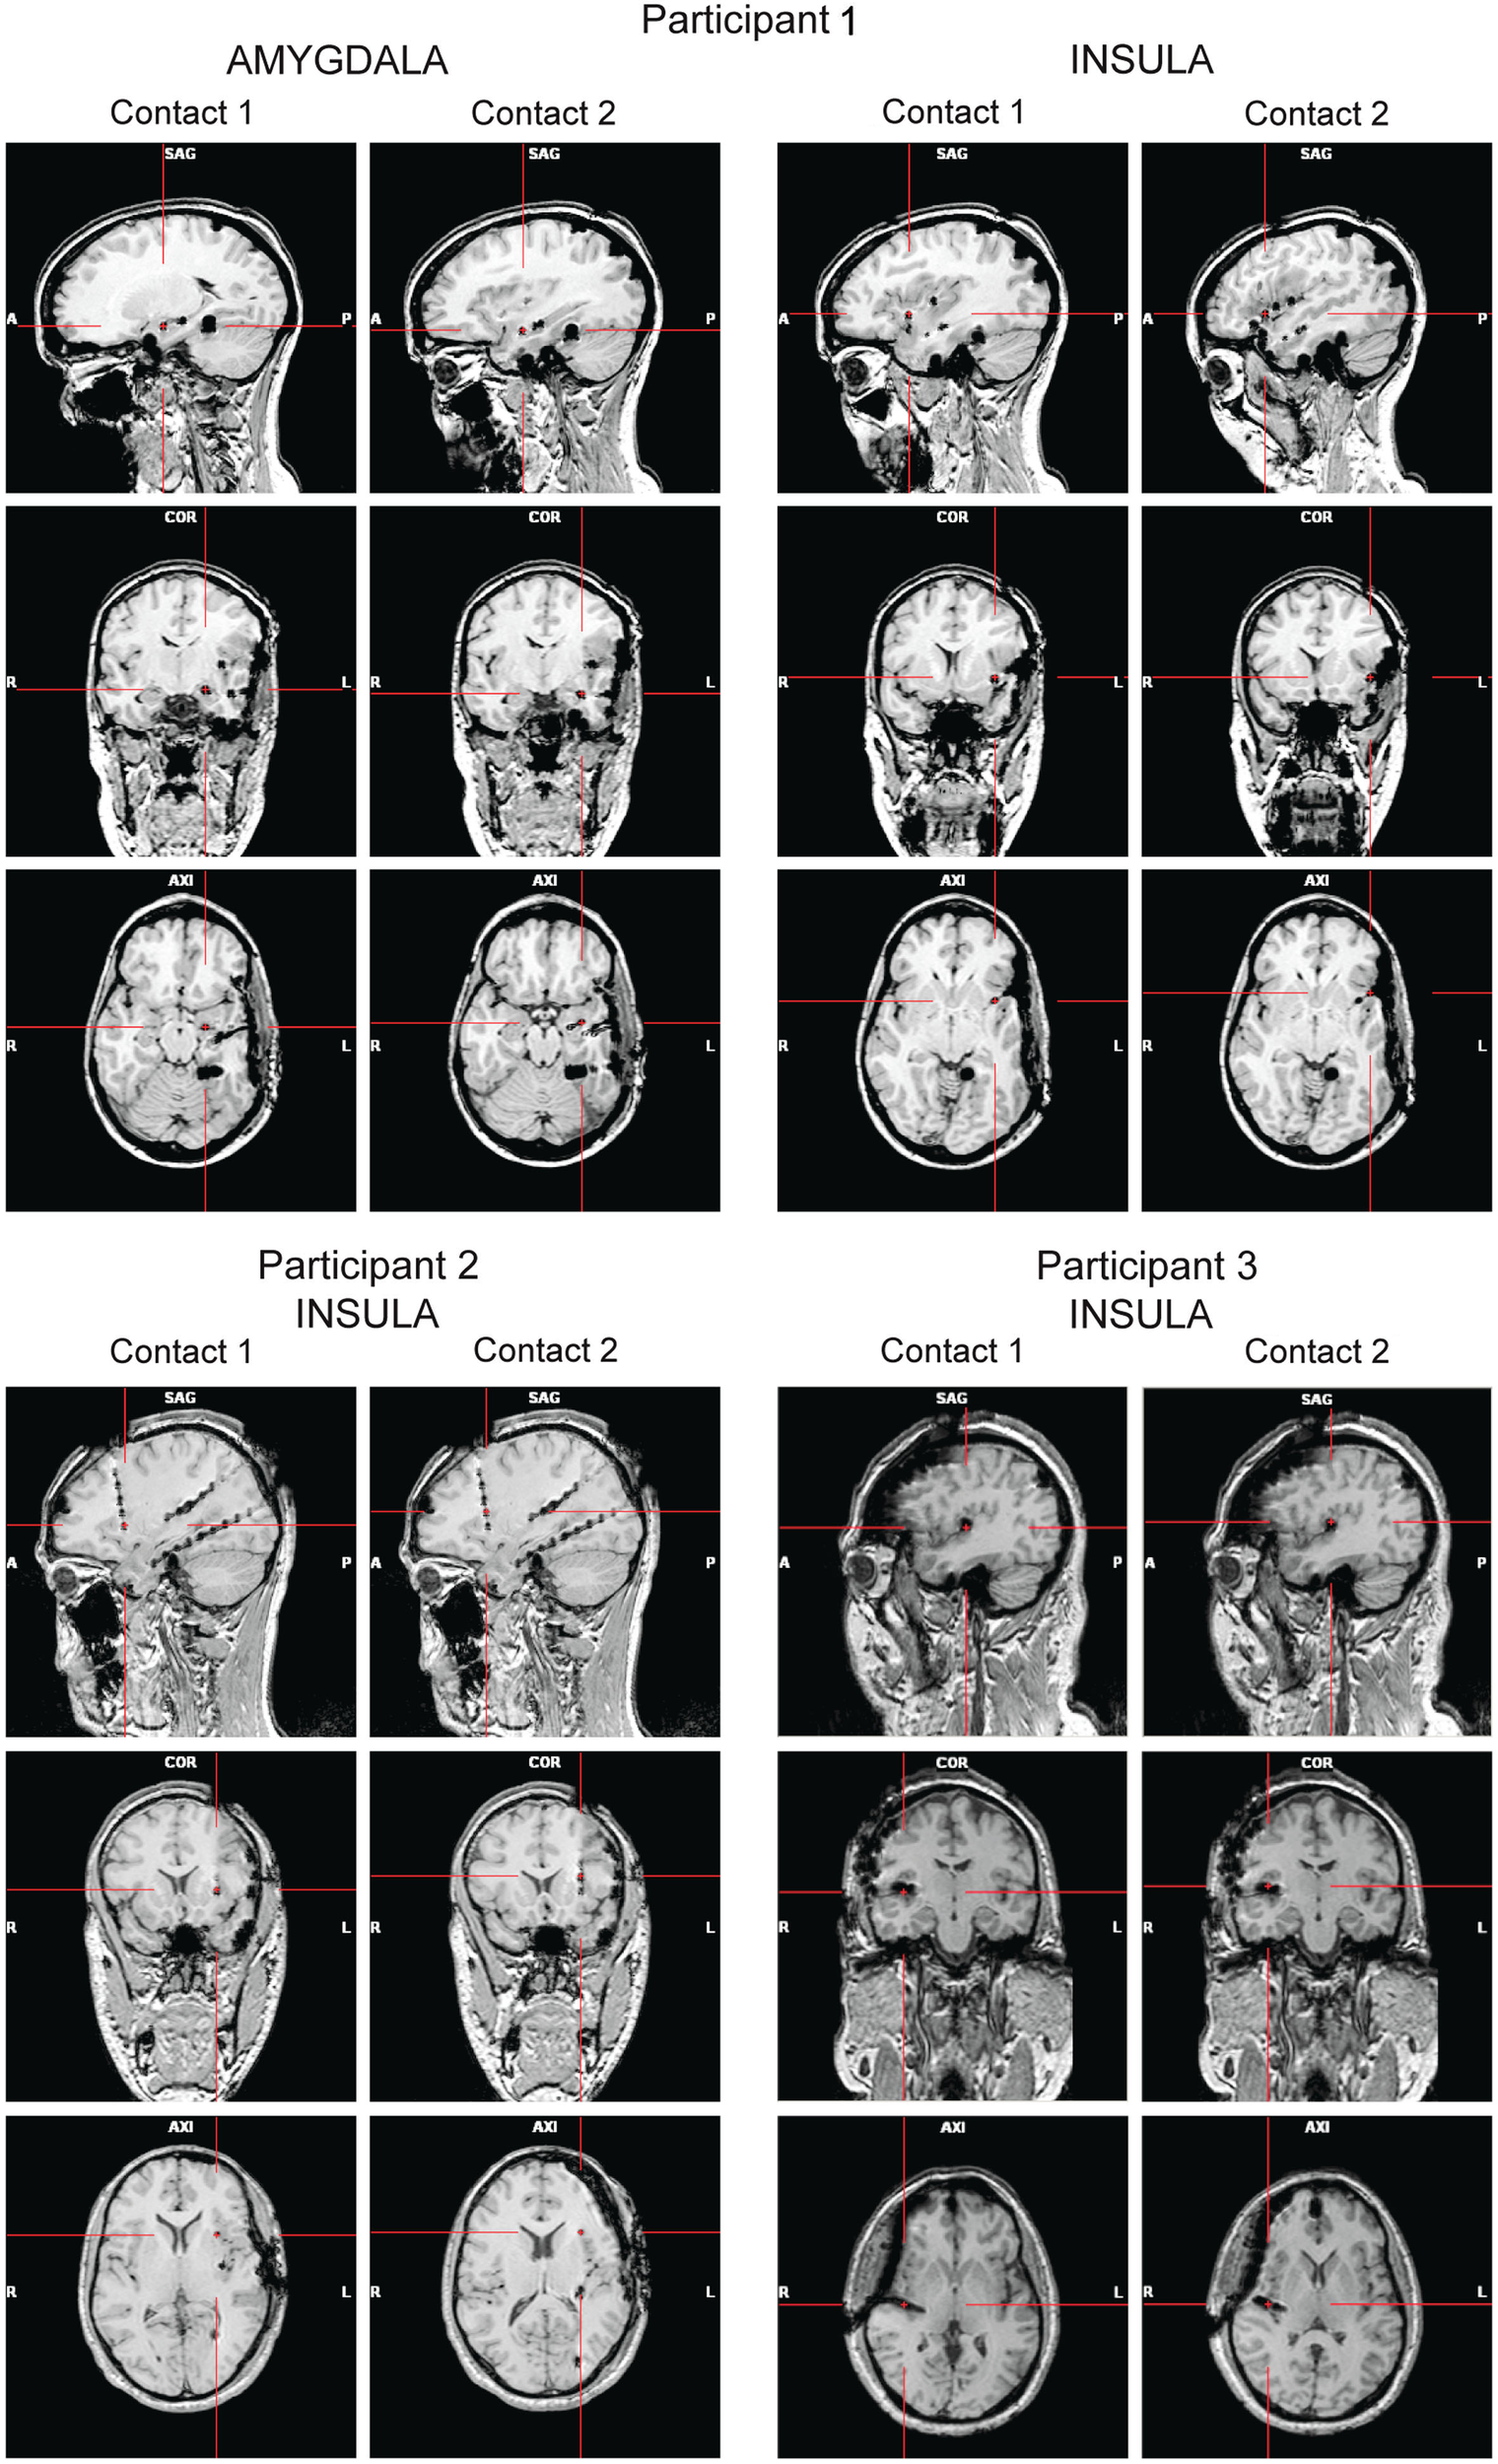

High-resolution MRIs with 1 mm-thick slices were obtained after the implantation to determine the exact position of the electrodes (Figure 1). A 3D representation of the electrodes with respect to the patient’s brain was generated using Grid View software (Stellate Systems Inc., Montreal, QC, Canada; see also Wang et al., 2005). In the analyses presented here we included two contacts per electrode implanted either in the anterior insula (Participants 1–3) or in the amygdala (Participant 1).

Figure 1. Panels show the locations of the electrode contacts of interest for each participant based on post-implantation MRIs (A, anterior; P, posterior; L, left; R, right).